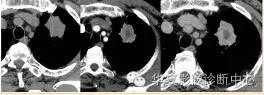

大家仔细看看这个中央不强化的腔内壁

你会发现内壁强化明显,边界清楚

一般这是炎性的脓腔,内层是肉芽肿,明显强化,分界清楚

癌肿的坏死一般是缺血性的,是肿瘤生长速度过快,中央带的血管受挤压,中央供血不足坏死的,一般边界模糊

内有内层强化,不会这么清楚

这是两者坏死的差异